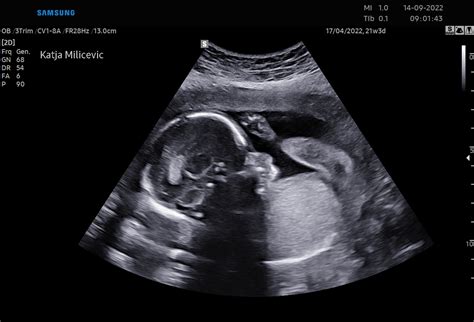

Rast ploda je fascinanten proces, ki se spremlja od oploditve do rojstva. V prvih tednih po spočetju se zarodek hitro deli in razvija ključne organe. Že v 5. do 6. tednu nosečnosti je mogoče na ultrazvoku videti srčni utrip. Do konca prvega trimesesečja zarodek meri približno 28 mm in se začne obdobje ploda.

V drugem trimesesečju plod hitro raste, razvijajo se prsti na rokah in nogah, spolni organi, začnejo se spontani gibi. V 20. tednu plod tehta okoli 300 gramov, na ultrazvoku so vidni obrazni gibi. Do 24. tedna se nalaga podkožno maščevje, razvijajo se pljučni mešički.